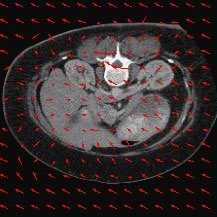

Transformers have made remarkable progress towards modeling long-range dependencies within the medical image analysis domain. However, current transformer-based models suffer from several disadvantages: (1) existing methods fail to capture the important features of the images due to the naive tokenization scheme; (2) the models suffer from information loss because they only consider single-scale feature representations; and (3) the segmentation label maps generated by the models are not accurate enough without considering rich semantic contexts and anatomical textures. In this work, we present CASTformer, a novel type of generative adversarial transformers, for 2D medical image segmentation. First, we take advantage of the pyramid structure to construct multi-scale representations and handle multi-scale variations. We then design a novel class-aware transformer module to better learn the discriminative regions of objects with semantic structures. Lastly, we utilize an adversarial training strategy that boosts segmentation accuracy and correspondingly allows a transformer-based discriminator to capture high-level semantically correlated contents and low-level anatomical features. Our experiments demonstrate that CASTformer dramatically outperforms previous state-of-the-art transformer-based approaches on three benchmarks, obtaining 2.54%-5.88% absolute improvements in Dice over previous models. Further qualitative experiments provide a more detailed picture of the model's inner workings, shed light on the challenges in improved transparency, and demonstrate that transfer learning can greatly improve performance and reduce the size of medical image datasets in training, making CASTformer a strong starting point for downstream medical image analysis tasks.